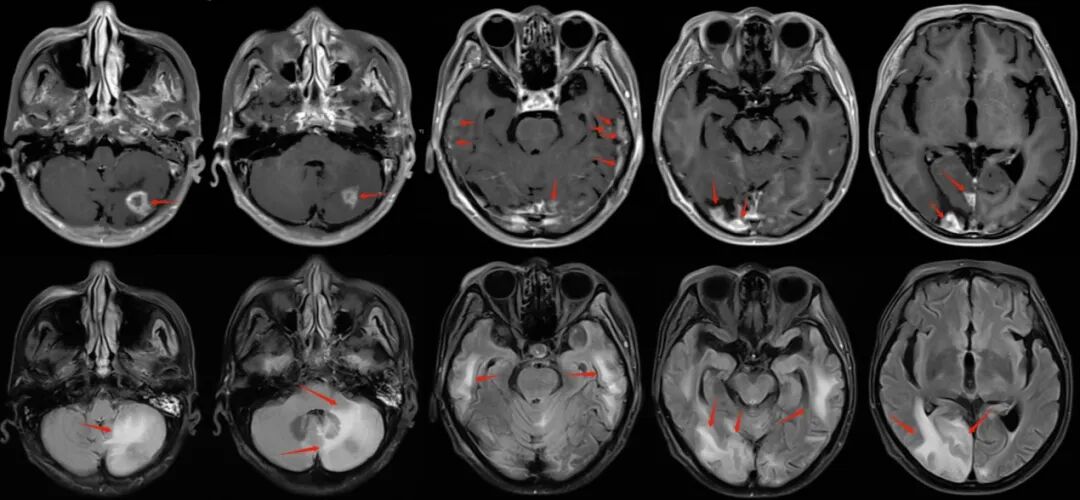

患者入院后磁共振檢查可見,左側(cè)小腦半球,雙側(cè)顳葉、雙側(cè)枕葉多發(fā)轉(zhuǎn)移病灶及轉(zhuǎn)移結(jié)節(jié);病灶區(qū)大片腦組織水腫。

圖注:磁共振檢查,上排為T1增強(qiáng)像,可見患者左側(cè)小腦半球,雙側(cè)顳葉、雙側(cè)枕葉多發(fā)明顯強(qiáng)化的轉(zhuǎn)移病灶及轉(zhuǎn)移結(jié)節(jié);下排為FLARE像,可見病灶區(qū)大片腦組織水腫。